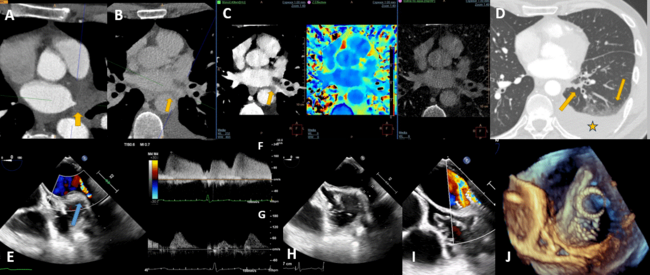

A 53-year-old man with a history of atrial fibrillation underwent a successful antral pulmonary vein isolation. After 6 months of follow-up, he was referred for exertional dyspnea. CT revealed a severe PVS of both left PVs (Figure A-C). Spectral CT reconstructions improved the visualization of the lumen of the severely stenotic veins. A balloon angioplasty was performed under TEE guidance. Both left stenotic PVs were identified with a flow of up to 2.1 m/s (Figure E, F, and H). Stent deployment and post-dilation were precisely monitored, and immediate complications were ruled out (Figure I-J; Videos 1-3). Stent position was evaluated in real-time. Flow velocities significantly decreased (0.8 m/s), and a predominant diastolic PV flow pattern was identified (Figure G). The patient was discharged without complications.

To the best of our knowledge, no reports on the role of TEE imaging during PVS dilation have been published to date. This case underscores its utility both for monitoring and screening complications, potentially improving long-term results.